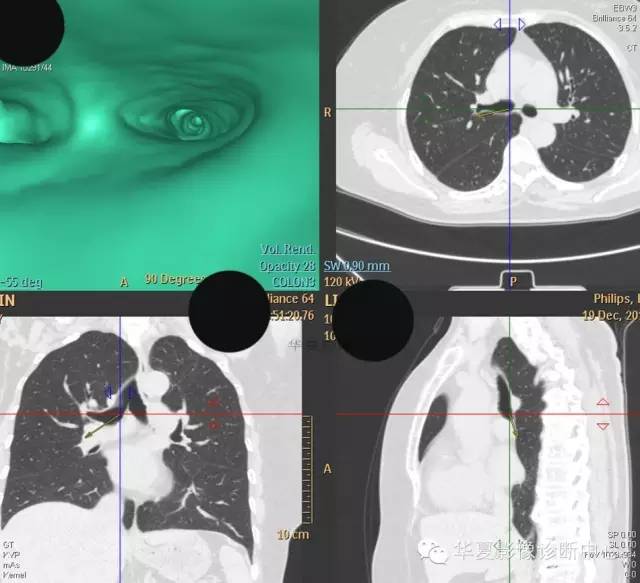

【病例学习】典型周围型肺癌CT病例一例

女,56岁,其父因肺癌去世,自觉胸部疼痛不适来诊要求拍胸片。

检查所见:

1.右肺上叶:肺组织1块,大小13×4×7cm。切面棕红色。2.右肺上叶肿物:灰白色组织一块,大小3×1×1.5cm。切面灰白色。3.右肺中叶结节:灰白色绿豆大组织1块。4.淋巴结:灰黑色绿豆大组织1块。

检查结论:

(右)肺中分化鳞状细胞癌。浸及胸膜。支气管残端切净。淋巴结未见癌转移(0/10)。